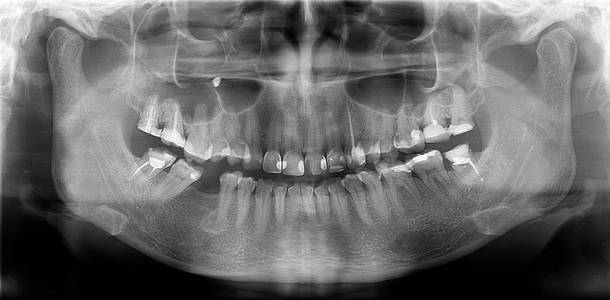

颌骨拍片

"聪明可靠"的口腔全景ct来喽!赶紧上车来"瞧瞧"

图片尺寸1021x627

正畸医生主要通过头颅定位片来观察颅骨,颌骨的长,宽

图片尺寸2541x2001